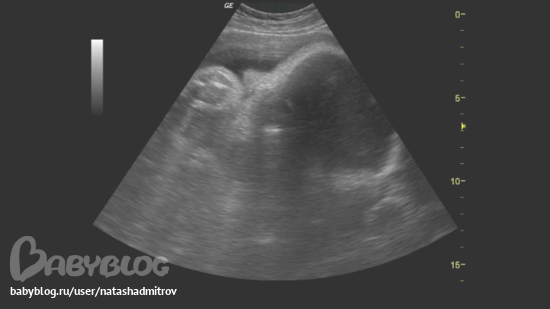

а вот И НАШЕ СОЛНЫШКО:

сосем ручку,